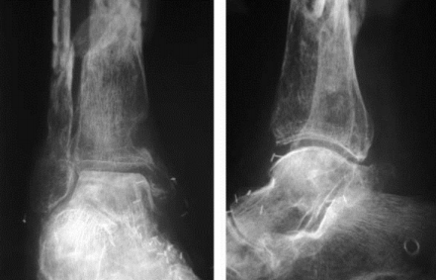

What disease is this? | Osteoarthritis |

What disease is this? | Rheumatoid arthritis |